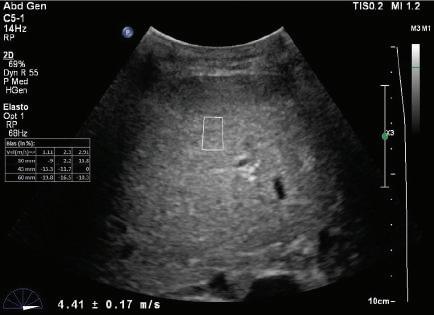

Longitudinal tissue compression results in the generation of transverse shear waves12,13 (see Fig. 1.22B). In shear wave elastography, shear waves are generated by repetitive compression produced by high-intensity pulses from the ultrasound transducer (see Fig. 1.22B). In contrast to longitudinal compressional waves that propagate very quickly in the human body (≈1540 m/sec), shear waves propagate slowly (≈1-50 m/sec). Shear waves are tracked with high frame rate images to determine their velocity. The propagation velocity of shear waves is directly proportional to Young modulus and provides a quantitative estimate of tissue stiffness14,15 (Fig. 1.24).

FIG. 1.24 Shear Wave Elastograms of (A) Normal and (B) Cirrhotic Liver. Shear wave velocities measured in liver tissue samples by shear wave elastography indicates a velocity of 1.29 ± 0.10 m/sec in the normal liver compared to a velocity of 4.41 ± 0.17 m/sec in the cirrhotic liver. Increased shear wave velocity is associated with increased tissue stiffness due to hepatic fibrosis. (Courtesy of P. O’Kane, Thomas Jefferson University.)

A - Normal liver

v = 1.29 ± -.10 m/s

B - Cirrhotic liver

v = 4.41 ± -.17 m/s